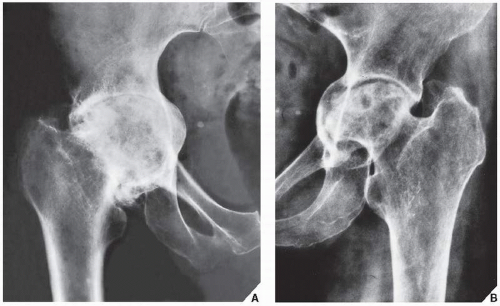

Фотографии и схемы: Коксит правого тазобедренного сустава